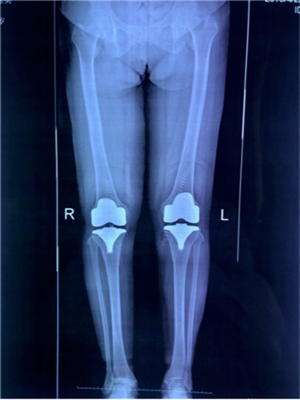

?。ㄊ中g(shù)前、手術(shù)后對(duì)比)

5月29日,徐阿姨如期進(jìn)行了雙側(cè)全膝關(guān)節(jié)同期置換術(shù)。術(shù)中發(fā)現(xiàn)徐阿姨膝關(guān)節(jié)退變嚴(yán)重,有大量的滑膜軟骨瘤,清除病變后又發(fā)現(xiàn)她前交叉韌帶缺失后交叉韌帶纖細(xì),即決定采用限制性較高的E1 AS墊片,該假體極大的提高了手術(shù)安全性,降低了手術(shù)風(fēng)險(xiǎn)和創(chuàng)傷,手術(shù)歷時(shí)2小時(shí),患者術(shù)后恢復(fù)良好。手術(shù)后第二天,徐阿姨就可以扶著助步器下地活動(dòng),目前已可以徒步行走、上下樓梯。